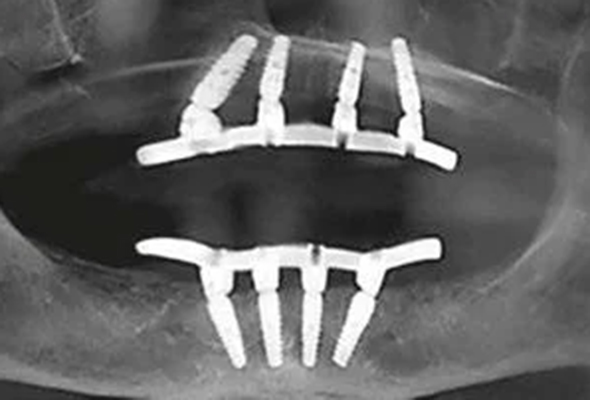

Conventional Implants vs Pterygoid Implants

Pterygoid Dental Implants are a specific type of dental implants that are used for full-mouth rehabilitation in patients with insufficient bone volume in the upper jaw. They are named 'Pterygoid' because they are placed in the pterygoid plate, which is part of the sphenoid bone at the back of the upper jaw.

Pterygoid Implants are longer than conventional implants, typically measuring between 15 to 20 millimeters. Their increased length provides added stability and allows them to harness support from the dense pterygomaxillary region, eliminating the need for sinus lift procedures or bone grafts, which are often required with other types of implants. Thus, they offer a viable and effective solution for patients who have been told they are not suitable candidates for traditional implants due to lack of bone mass.

As Pterygoid Dental Implants are anchored in the pterygoid plates, they provide a firm and stable foundation for prosthetic teeth, ensuring optimal functionality and appearance.